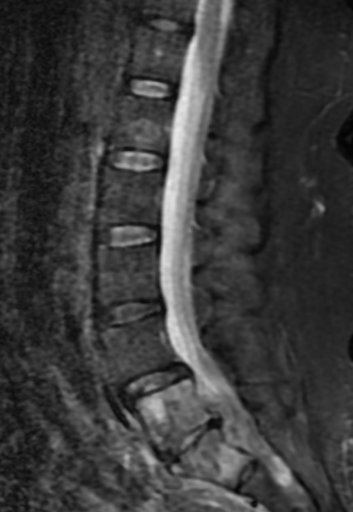

Case Presentation: A 56-year-old female with a history of cervical cancer in remission, post-chemotherapy and total hysterectomy, and insulin-dependent diabetes mellitus, was admitted for worsening chronic lower back pain, which had intensified over the past two weeks. She denied paresthesia or weakness. On examination, she was diaphoretic, shivering, and afebrile, with a blood pressure of 159/112 mmHg and a heart rate of 154 beats/minute. There was diffuse tenderness in the lower back, but no neurological deficits. Initial labs showed leukocytosis (20,450/mm³ with a left shift), lactic acid of 3.1 mmol/L, bicarbonate 10mmol/L, glucose of 456 mg/dL, and ketonuria, suggesting diabetic ketoacidosis. Blood and urine cultures were obtained, and broad-spectrum antibiotics (Cefepime and vancomycin) were initiated for suspected pyelonephritis. The patient was admitted to the ICU for diabetic ketoacidosis management.A CT of the abdomen and pelvis with contrast revealed right-sided hydroureteronephrosis, without calculi, and a nephrostomy tube was placed. As her back pain persisted with a new onset of muscle cramps in her lower extremities an MRI of the thoracic and lumbar spine was ordered that revealed osteomyelitis, discitis at the L5-S1 level, and an anterior epidural abscess (2.3 x 0.9 cm), causing canal stenosis. She was transferred to a neuro-ICU for neurosurgical evaluation. Cultures from the urine grew Klebsiella pneumoniae and Escherichia coli, and blood cultures identified Streptococcus constellatus. Based on sensitivity results, antibiotics were narrowed to Ceftriaxone.The neurosurgeon recommended non-surgical management, as the patient’s back pain improved, and her neurological exam remained normal. Further investigations, including Maxillofacial CT and Transesophageal Echocardiogram, revealed no abscess or vegetation, respectively. A bone biopsy confirmed acute osteomyelitis, but no malignancy. Cultures from the biopsy and repeat blood cultures showed no growth, and inflammatory markers (ESR, CRP) downtrended. The patient was discharged on IV Ceftriaxone (2 grams daily) to complete a seven-week course.